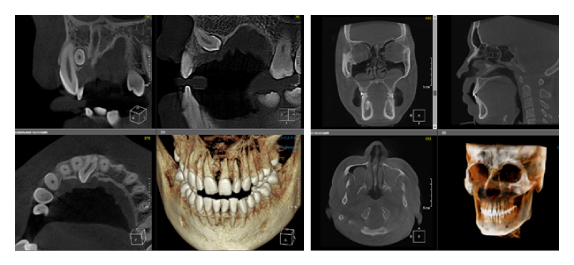

Когда мы отправляем пациента на проведение рентгенологического исследования, то подвергаем его определенному риску. Именно это нужно осознавать, так как в радиологии нет минимально безопасной дозы, поэтому любое назначение должно быть обоснованным. В связи с этим поле обзора является достаточно принципиальным параметром. Если вы врач-терапевт, занимающийся эндодонтией или ортопед, который решил оценить состояние зубов перед протезированием, то вы должны понимать, что проведение исследования с полем обзора 10x10 см будет гораздо информативнее нежели большие снимки (18x16 см и выше). В первую очередь это связано с размером вокселя, о нём я напишу чуть ниже, а второе это то, что вам придется увеличивать изображение по каждому корневому каналу, и от этого вы будете терять в качестве снимка (рис. 1). И ситуация наоборот, если вы ортодонт, то чтобы использовать весь диагностический потенциал, а также возможность загрузить данные для расчёта 3D цефалометрии, то вам нужны снимки, захватывающие весь лицевой отдел черепа. Таким образом, дентальный томограф должен обладать возможностью проведения исследований с разным FOV, обеспечивая нужды всех специалистов. Если ваша клиника базируется на терапевтическом, хирургическом и ортопедическом приёме, то на мой взгляд, можно рассмотреть дентальные томографы с полем обзора 10x10 см или 16x10 см. Последний больше актуален для тех, кто работает с ВНЧС, так как антропометрически в 16 см даже у брахицефалов сустав должен попадать. Если в клинике есть ортодонтическое направление, функциональная стоматология, ЛОР-практика или ЧЛХ, то, безусловно, вышепредставленные снимки не будут отражать всех данных, которые необходимы для диагностики и планирования лечения. Здесь лучше рассмотреть конусно-лучевые компьютерные томографы с зоной сканирования 18x16 или 20x20 см. Особо стоит отметить понятие «сшивки». Есть дентальные томографы, которые делают один цельный снимок размерами, которые описаны выше, а есть аппараты, которым нужно провести две экспозиции и сшить изображения вместе, чтобы получился необходимый объём исследования. Как правило, вторые томографы чуть дешевле, но всё зависит от того, насколько вам нужна максимальная точность исследования. Если при сшивке челюсти и зубы, как правило, совмещаются практически идеально, то на уровне позвоночного столба происходит наслоение тканей и от него уже не избавиться (рис. 2). Второй отрицательный момент – это износ оборудования, логично, что он будет быстрее, так что экономия средств — это ещё спорный вопрос.

Рис. 1. Представлены два исследования (10x10 см и 20x20 см). На обоих изображениях хорошо видна канально-корневая система зубов, но, если масштабировать второе исследование, то качество неминуемо снизится, как и диагностическая эндодонтическая эффективность.